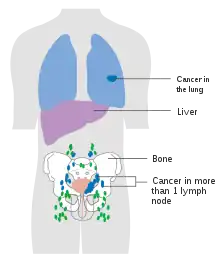

The most common sites for bladder cancer metastases are the lymph nodes, bones, lung, liver, and peritoneum.[78] The most common sentinel lymph nodes draining bladder cancer are obturator and internal iliac lymph nodes. The location of lymphatic spread depends on the location of the tumors. Tumors on the superolateral bladder wall spread to external iliac lymph nodes. Tumors on the neck, anterior wall and fundus spread commonly to the internal iliac lymph nodes.[79] From the regional lymph nodes (i.e. obturator, internal and external lymph nodes) the cancer spreads to distant sites like the common iliac lymph nodes and paraaortic lymph nodes.[80] Skipped lymph node lesions are not seen in bladder cancer.[79]